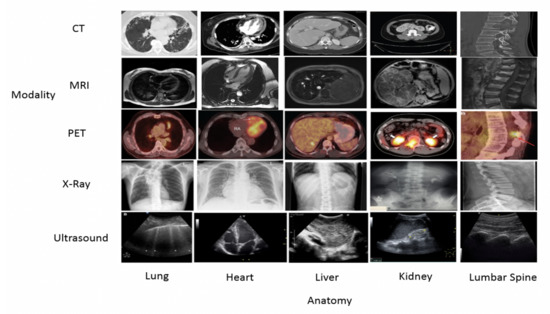

3.1. Data Collection